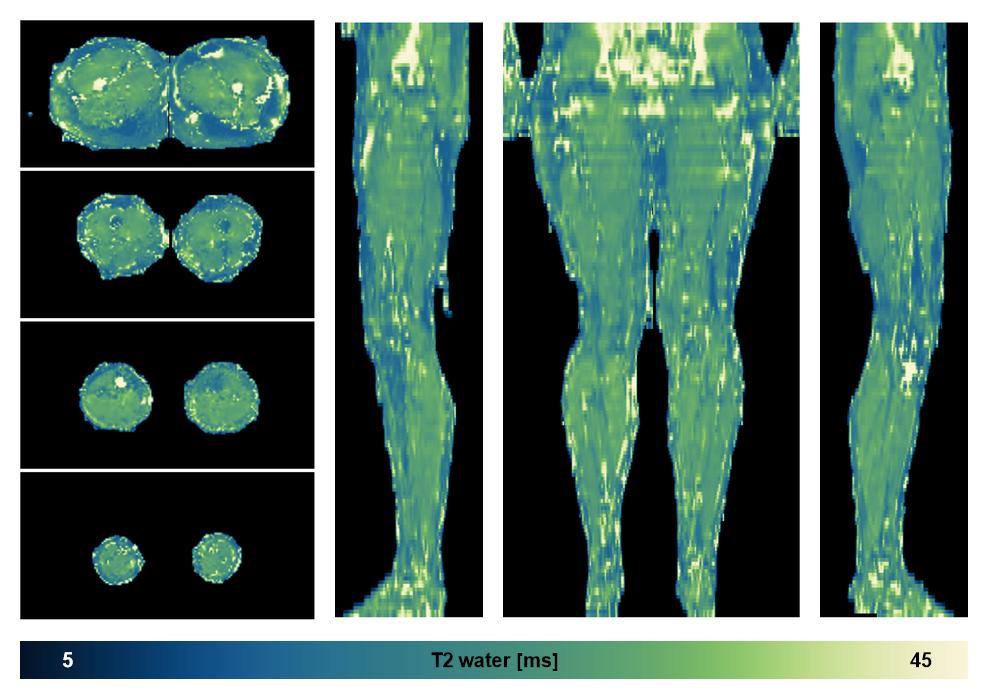

Water only T2 mapping

Multi echo spin echo T2 relaxation time mapping with EPG reconstruction, for information look here».

• Water only signal

The water part of the acquired multi-echo spin echo data.

• Water only T2 relaxation time

The water only T2 relaxation time of the lower extremity obtained from multi echo spin echo t2 mapping with EPG based reconstruction.